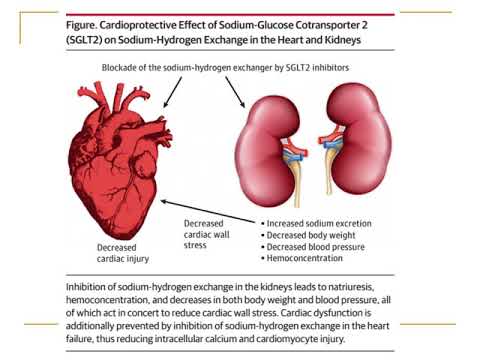

Tratamiento con inhibidores del co-transportador Na / glucosa en pacientes con IC. Dra. María Eugenia Döppler. Residencia de Cardiología. Hospital C. Argerich. Buenos Aires